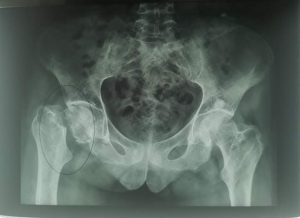

صوت العدالة – فوزي حضري تمكن فريق طبي وتمريضي متخصص في طب وجراحة العظام والمفاصل ، بالمركز الاستشفائي الإقليمي لتاوريرت، هذا اليوم الأحد 08 دجنبر 2019، من إجراء أول عملية [...]